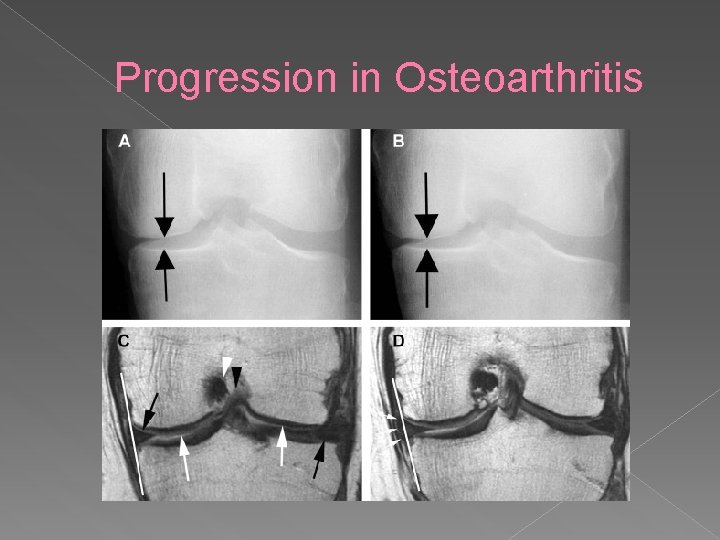

Progression in Osteoarthritis

Progression in Osteoarthritis